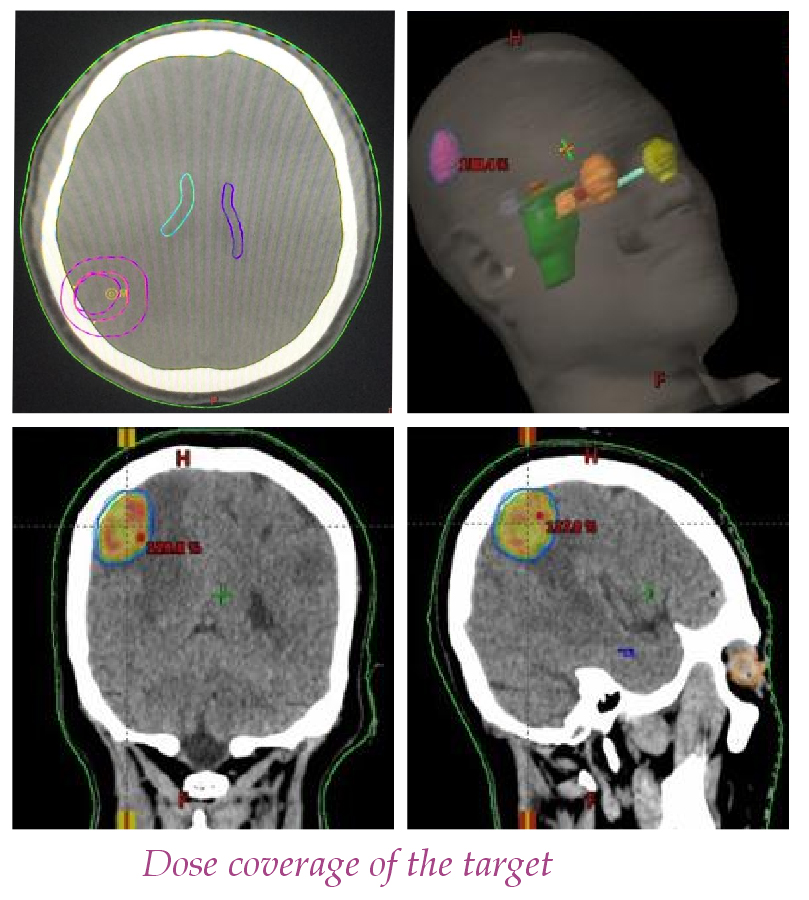

In a significant development in cancer care during COVID-19 pandemic, Dr B Borooah Cancer Institute, Guwahati has started Stereotactic Radio Surgery for the first time in North-East India on 17th July. A 56 year old female patient of primary lung cancer with single brain metastasis measuring 2.2 x 2 cm in the right parietal lobe of the brain was treated with the whole brain radiotherapy followed by a very high dose of radiotherapy in a single fraction which is known as stereotactic radiosurgery. It was carried out by using VMAT and 6XFFF Beams.